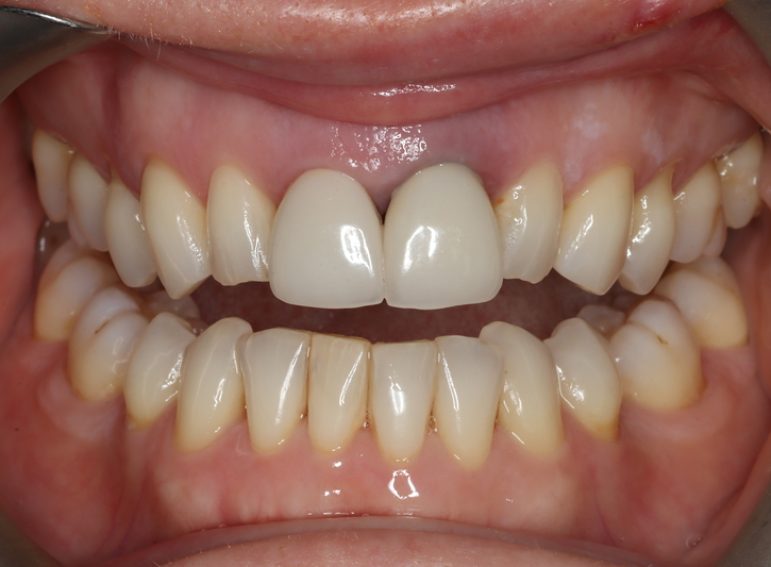

Surgical management of external cervical resorption.